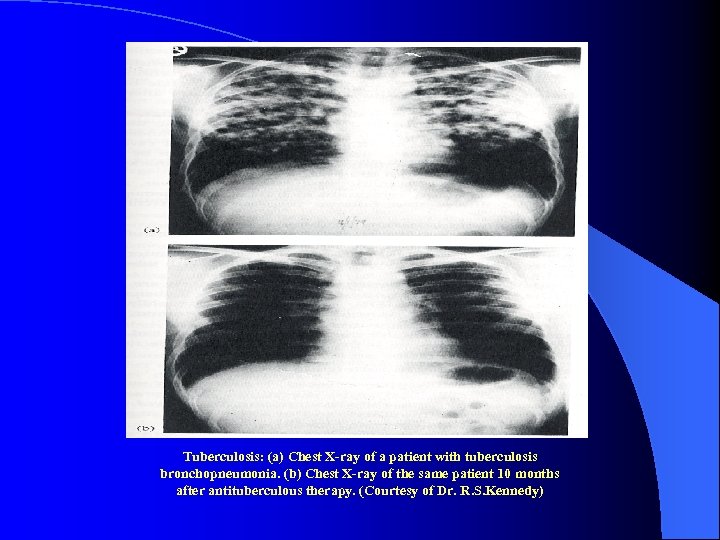

Tuberculosis: (a) Chest X-ray of a patient with tuberculosis bronchopneumonia. (b) Chest X-ray of the same patient 10 months after antituberculous therapy. (Courtesy of Dr. R. S. Kennedy)